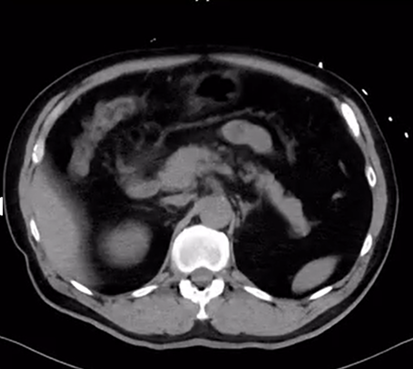

55歳男性。腹痛のため救急車で来院。腹痛精査のためCT撮影。CTから帰ってくると左上肢が動かしにくいと言っている。

単純CT

大動脈が割れている。左上肢麻痺が出現→Stanford Aを疑い、造影CT準備と心外コンサルトを同時に考える。降圧も合わせて行いながら動いていく。